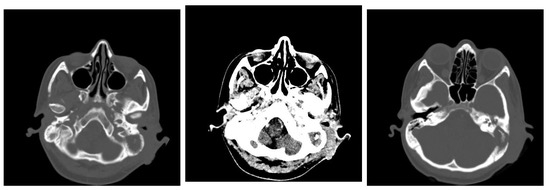

3.1.2. Computed Tomography and Magnetic Resonance Imaging

| CT Aspects | Number of Patients | Percentage |

|---|---|---|

| Fluid accumulation | 168 | 100% |

| Osteolysis | 152 | 90.47% |

| Osteocondensations | 128 | 76.19% |

| Cholesteatoma | 48 | 28.57% |

| Exocranial extensions | 48 | 28.57% |

| Intracranial extensions | 24 | 14.28% |

| Changes to the external auditory canal | 68 | 40.47% |

| Ossicular chain damage | 144 | 85.71% |